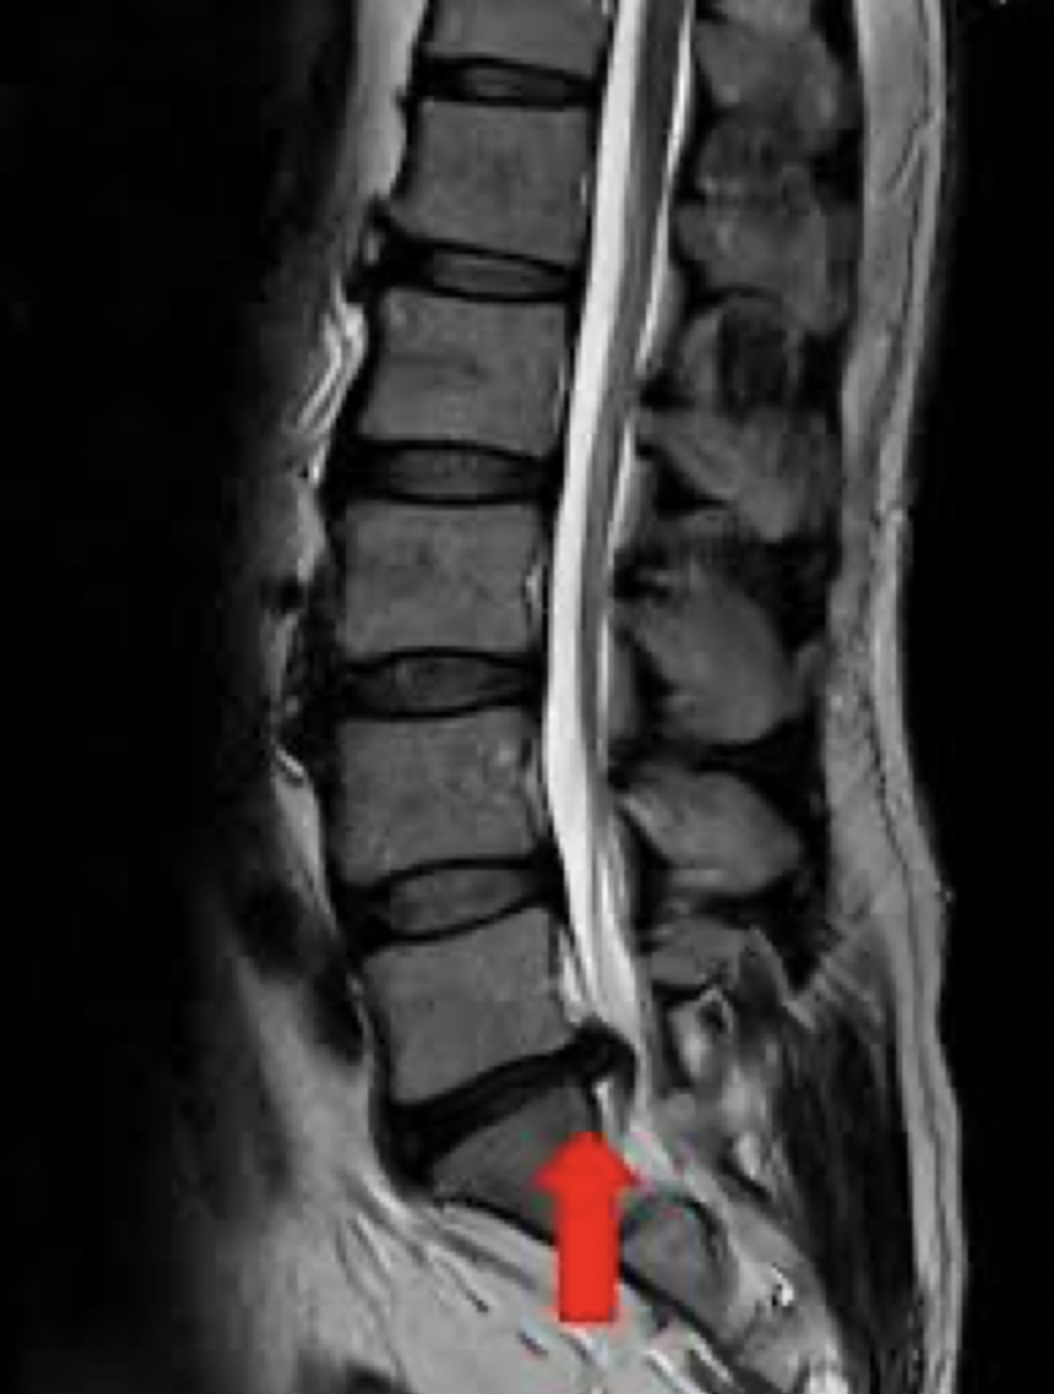

検査時間が短く、高性能、高画質の1.5テスラMRI装置を導入しています。

腰椎椎間板ヘルニア